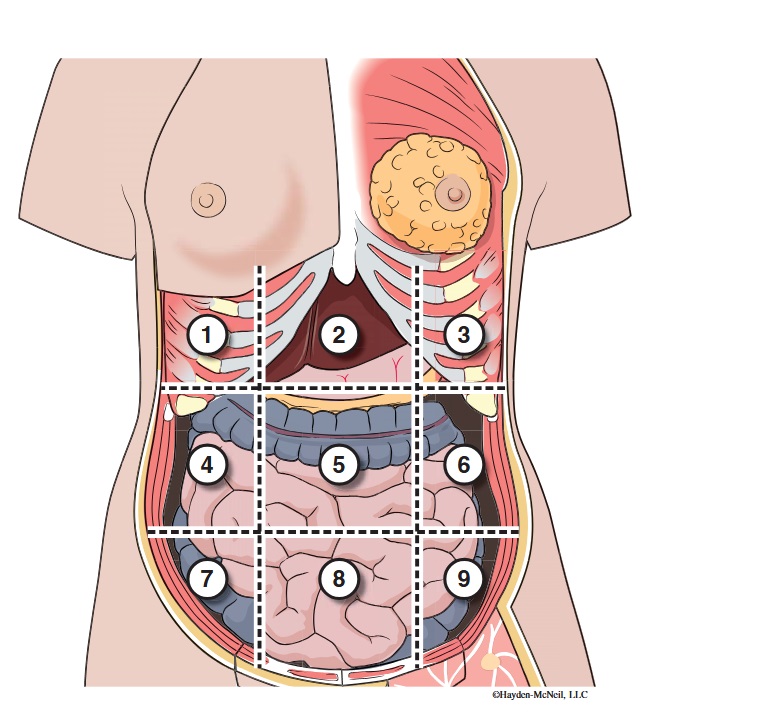

What abdominal region is labeled #1?

right hypochondriac

What abdominal region is labeled #2?

epigastric

What abdominal region is labeled #3?

left hypochondriac

What abdominal region is labeled #4?

right lumbar

What abdominal region is labeled #5?

umbilical

What abdominal region is labeled #6?

left lumbar

What abdominal region is labeled #7?

right iliac/ inguinal

What abdominal region is labeled #8?

hypogastric

What abdominal region is labeled #9?

left illiac/ inguinal

What organs are apart of the right hypochrondriac region?

right lobe of liver, gallbladder, right adrenal gland

What organs are apart of the epigastric region?

pyloric end of stomach, duodenum, pancreas

What organs are apart of the left hypochondriac region?

stomach, spleen, left adrenal gland

What organs are apart of the right lumbar region?

ascending colon, right kidney, portion of small intestine

What organs are apart of the umbilical region?

omentum, mesentery, small intestine

What organs are apart of the left lumbar region?

descending colon, left kidney, portion of the small intestine

What organs are apart of the right iliac/ inguinal region?

cecum of large intestines, appendix, right ovary

What organs are apart of the hypogastric region?

ileum, bladder, uterus

What organs are apart of the left iliac/ inguinal region?

sigmoid colon, left ureter, left ovary